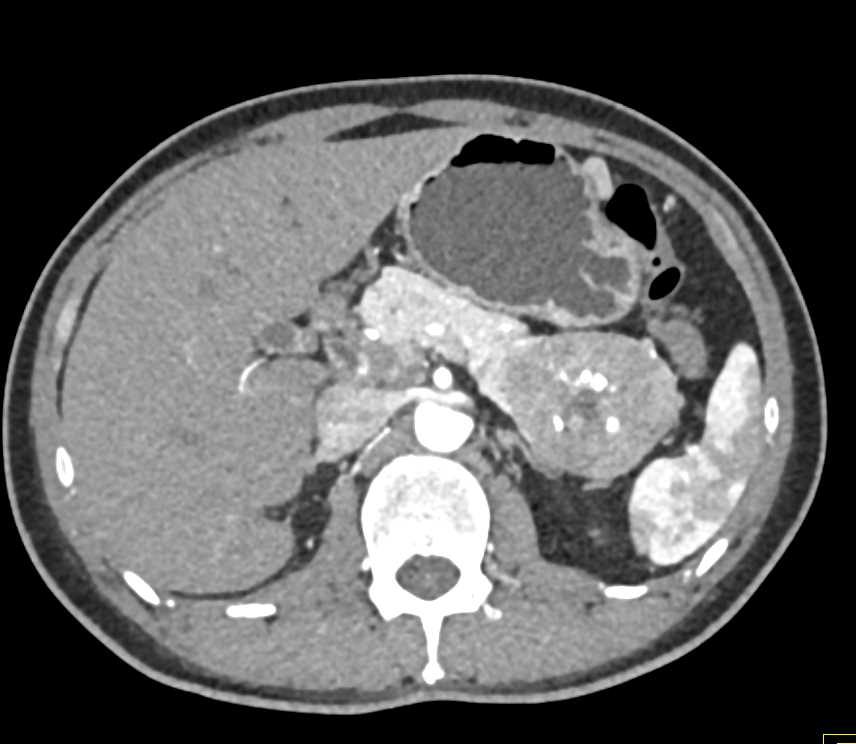

PNET Tail of the Pancreas